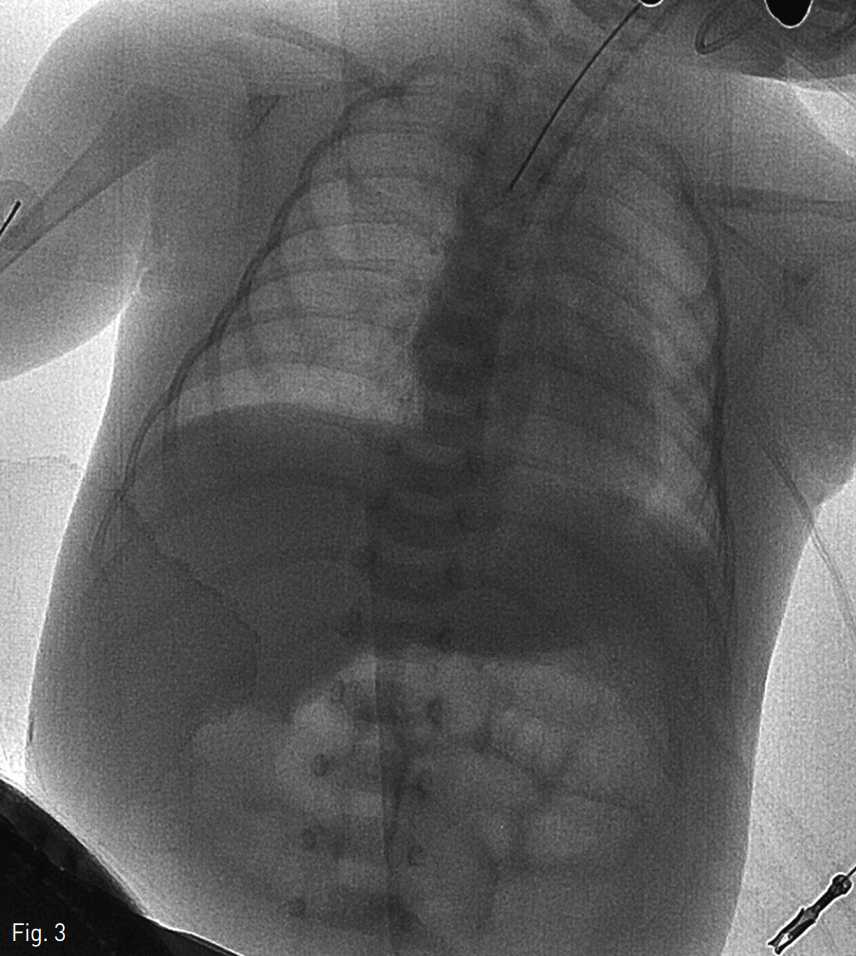

환아는 인터벤션 시술실로 이동하였고 18G 주사침으로 제대정맥을 천자하였으며 조영제를 주입하여 성공적인 천자와 제대정맥관의 위치를 확인하였다. 0.035-inch 유도철사를 넣고 주사침을 5 Fr 소아용 혈관초(Cordis, Miami, FL, USA)로 교체하였다. 이후 10mm의 직경을 가진 Amplatz gooseneck snare kit(EV3, Plymouth, MN, USA)를 제대정맥 내로 주입하였다. 이후 조심스런 여러 번의 시도 후에 제대정맥관의 끝부분을 잡는 것에 성공하였고 천천히 제대정맥 바깥쪽으로 제거하였다 (Fig. 2). 제대정맥관의 성공적인 제거는 투시화면상으로도 확인하였다 (Fig. 3).

Fig. 3

Final fluoroscopic image demonstrating removal of the broken UVC